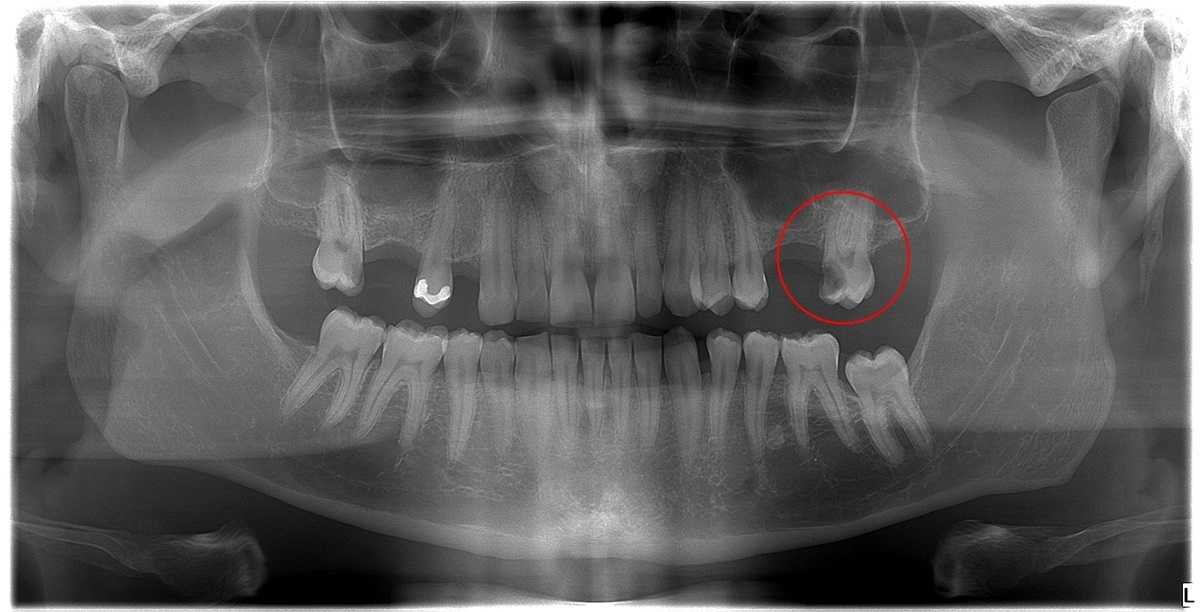

Bár nyilván előfordul, hogy a gyökérkezelés ellenére nem marad meg a fog, a gyakorlatban a fogak túlnyomó többségét hosszú évekre, sőt élethossziglan meg lehet menteni a gyökérkezeléssel. Egy tapasztalt szakember ugyanis fel tudja mérni, érdemes-e belevágni a gyökérkezelésbe, vagy a szuvasodás és/vagy gyulladás már akkora kárt tett a fogban, hogy menthetetlennek bizonyul.

Ráadásul a mikroszkópos gyökérkezelés megjelenésével a korábban már menthetetlennek ítélt fogak jó részét is meg lehet őrizni a tulajdonosuk számára. Erről számos esettanulmányunk is tanúskodik!